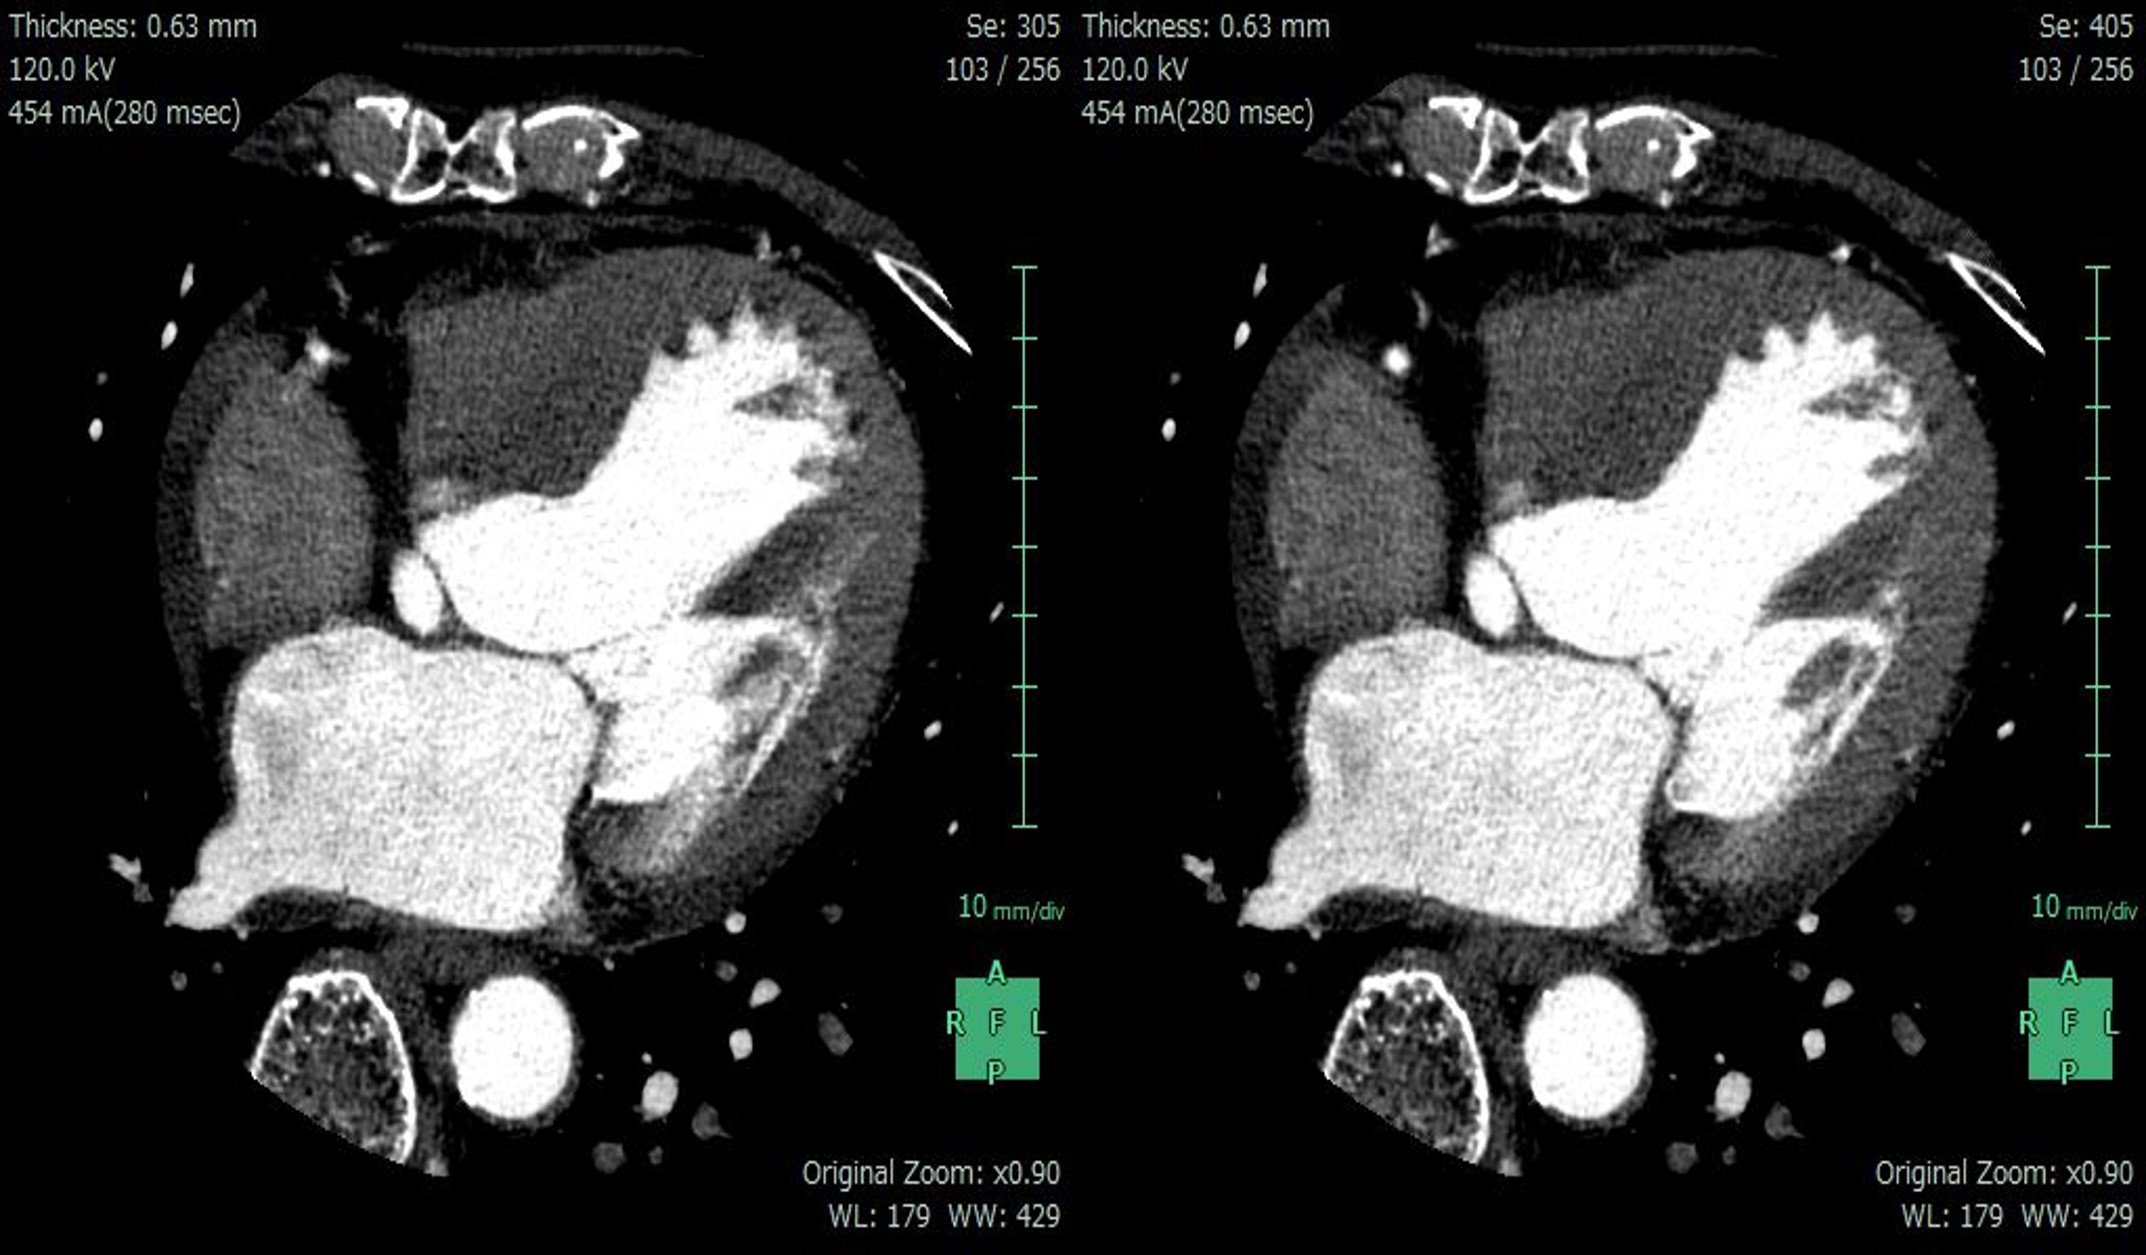

当院ではRevolution CTの他に他社ワイドカバレッジCTを導入しているが、CABG後を除きその殆どをRevolution CTで検査実施している。Revolution CTではSmart Phase(最適心位相探し)とSSF2.0(冠動脈および心臓全体静止アルゴリズム)を併用することで,80%以上の症例で最適心位相の検索が不要となり,撮影後のスループットが大幅に向上している。解析不能例は殆どないが、解析不能の原因としては造影コントラスト不良例のみである(図3) 。 実際の画像もほとんどの症例において冠動脈を静止できており、高HR症例や既存装置で苦慮していたHR70付近の症例でも、1心拍のみの撮影でしっかりと冠動脈を静止できている(図4) 。また、多少の息止め不良患者においても、冠動脈の動きは大幅に改善され安定した画像を提供できており、SSF2.0には大きな信頼を置いている。

このように、SSF2.0のおかげでよほどのことがない限り複数心拍での撮影は不要であり、同時にTFIを併用することで大きな被ばく低減を可能としている。

RevolutionCT_Sasebo04.jpg

図4. SSF2.0(左:OFF,右:ON)HR:90